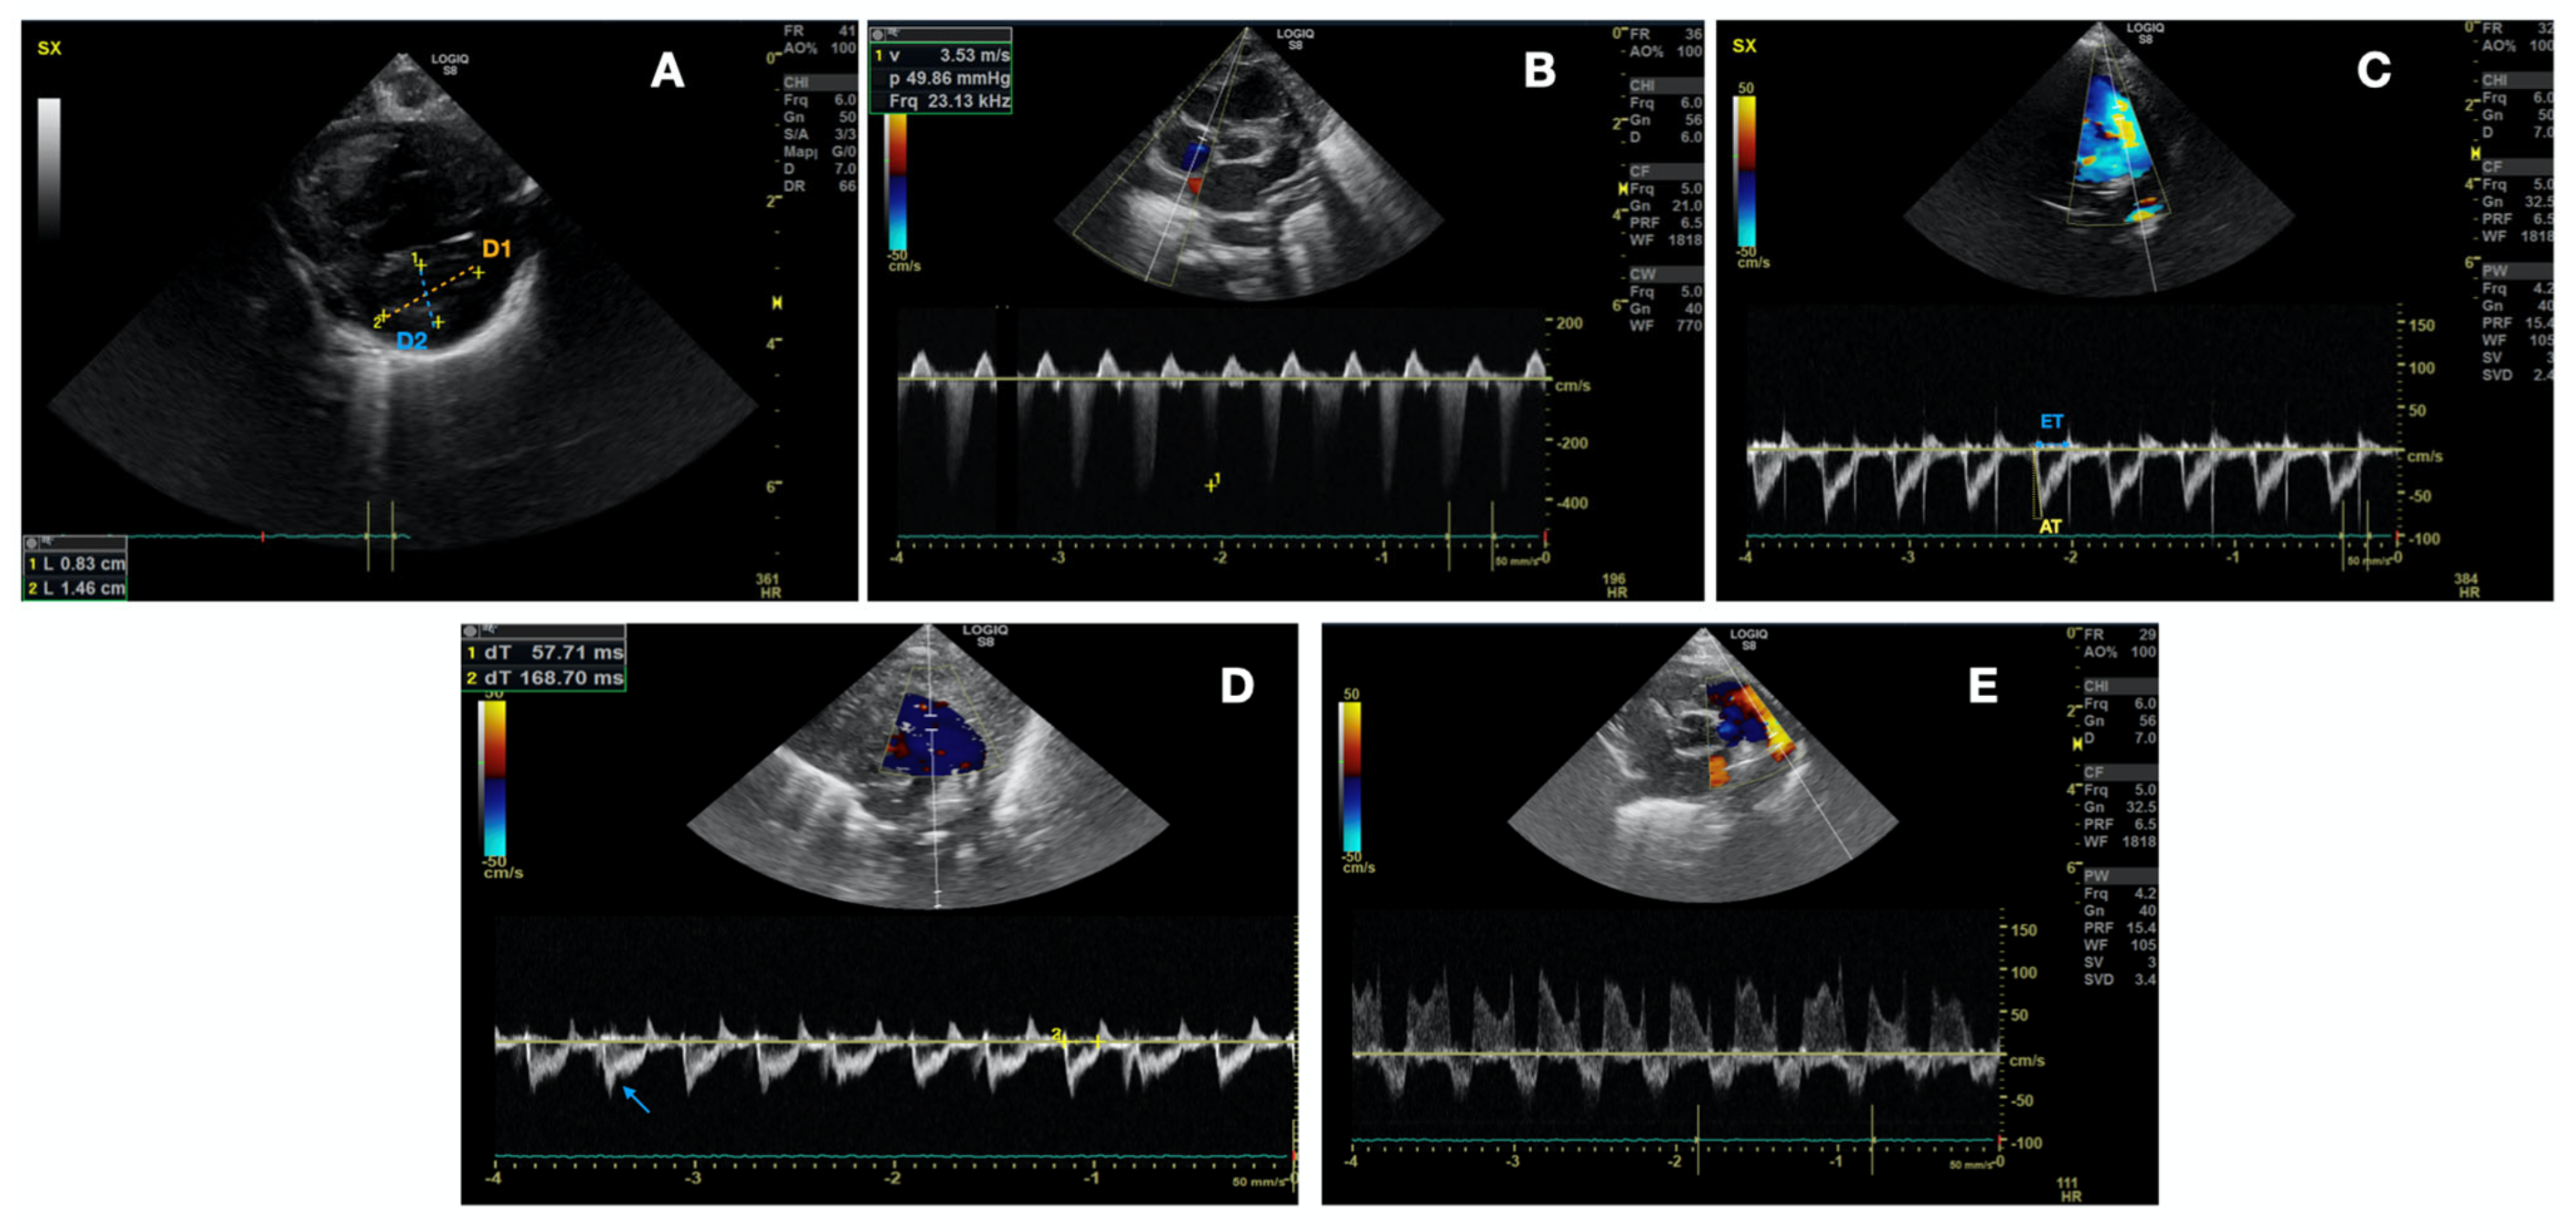

- Left ventricle telesystolic eccentricity index (EI) > 1.15 (Figure 2A). EI was obtained from the parasternal short axis at the mid-papillary muscle level. The formula (EI = D2/D1) was used, where D1 is the ventricular diameter perpendicular to the interventricular septum bisecting D2, the diameter parallel to the interventricular septum [28]. As the right-to-left ventricular pressure ratio increases, septal curvature typically flattens and may even reverse curvature, providing higher EI.

- Pulmonary artery pressure-systolic (PAPs) systemic or supra-systemic (Figure 2B). PAPs estimation was based on Doppler measurement of tricuspid regurgitation and pulmonary regurgitation jet on parasternal short axis view. The velocity at end-diastole (at the QRS complex on the ECG) is converted into a pressure gradient through the modified Bernoulli equation: (RVSP = 4 × v2), where v is the maximum velocity of the tricuspid valve regurgitation jet measured using continuous wave (CW) Doppler. Right atrial pressure was ignored.

- Pulmonary artery acceleration time to right ventricular ejection time ratio (PAAT/RVET) < 0.3 (Figure 2C) +/− pulmonary notch (Figure 2D). PAAT/RVET was taken on the parasternal short axis view or parasternal long axis [29]. Pulmonary artery acceleration time (PAAT) is defined as the interval between the onset of systolic pulmonary arterial flow and peak flow velocity. Right ventricle ejection time (RVET) is the interval between the onset of right ventricle ejection to the point of systolic pulmonary arterial flow cessation. PAAT may be shortened in the case of increased PVR for several reasons: enhanced early pulmonary ejection, increased pulmonary vascular resistance, and loss of lung compliance leading to a rapid increase and reduction of flow velocity. PAAT, in fact, represents pulmonary flow acceleration, which increases as the vascular resistance is augmented, based on Newton’s law of motion. Therefore, the time to peak velocity in the pulmonary artery decreases and PAAT shortens, while the ejection time stays the same, causing a decreased PAAT/RVET ratio.